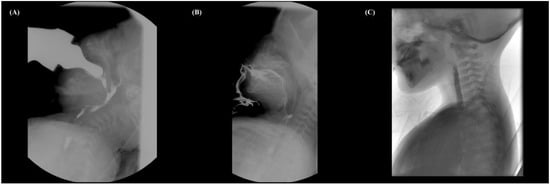

Figure 2. VFSS of patient 2. (A) VFSS on the 42nd day after birth with a bottle of milk (IDDSI level 0). The initiation of pharyngeal swallowing was severely delayed, the soft palate elevation was reduced, and repeated aspiration into the airway without a cough reflex (PAS 8) was observed. (B) VFSS at 10 months using pureed foods (IDDSI level 4). Food spilled beyond the chin due to poor lip closure, and minimal bolus preparation or transport occurred. Laryngeal elevation and epiglottic movement were partially improved so that there was no aspiration or penetration (PAS 0), with some pharyngeal residue. (C) VFSS at 2 years (35 months) using a scrambled egg (IDDSI level 5). Although she exhibited weak, slow, and prolonged mastication, she has demonstrated safe and efficient swallowing with a well-formed bolus.

A girl born through normal delivery without complication at 39 weeks gestation was admitted to the outpatient clinic on the 37th day after birth due to decreased sucking power and cyanosis during bottle feeding. When she breathed, stridor was heard, oxygen saturation dropped to 85% intermittently, and mild laryngomalacia was suspected upon laryngoscopy examination. Her clinical features included generalized hypotonia and micrognathia. At 42 days of age, a VFSS test performed using a bottle of milk (IDDSI level 0) showed a severe delay in initiation of pharyngeal swallowing and decreased soft palate elevation. In addition, there was the minimal laryngeal elevation and epiglottic movement. Most of the contrast remained in the pyriform sinus, with a narrow column of contrast remaining in the laryngeal vestibule, resulting in repeated aspiration into the airway without a cough reflex (PAS 8) (Figure 2A). Because she suffered from repeated pneumonia and sepsis, she relied primarily on nasogastric tube feeding. We started dysphagia rehabilitation therapy twice a week for 30 min or longer. She was observed to hyperextend her neck when eating and exhibited a weak sucking reflex that was not coordinated between sucking, swallowing, and breathing. We trained the parents to maintain her semi-upright posture while supporting her head and neck. A sucking reflex was induced by gently stroking the palate using the therapist’s finger, and a small amount of mild bolus was used to provide a coordinated sucking experience [10].

A follow-up VFSS test was performed using milk (IDDSI level 0) and oatmeal (IDDSI level 4) at 5 months of age. She frequently refused to suck on the nipple of the bottle and spat out most of the milk. She showed a similar pattern when oatmeal was given with a spoon. There was no significant improvement in VFSS findings. Because she exhibits food intolerance and minimal chewing responses when given food, we massaged the oral structures to promote tongue and lip movements and provide a variety of sensory stimuli to elicit a swallowing response. Additionally, neuromotor electrical stimulation was used to strengthen the anterior neck muscles in the same method as in patient 1. When swallowing was induced by using pureed foods, pharyngeal swallowing occurred at a faster rate than before with a reduced cough reflex. At 10 months, when the VFSS was performed using pureed foods (IDDSI level 4), food spilled due to poor lip closure and minimal bolus preparation or transport occurred, resulting in minimal clearance of the bolus in the oral cavity. Laryngeal elevation and epiglottic movement were partially improved so that there was no aspiration or penetration with pureed food; however, there was some pharyngeal residue (Figure 2B).

At the age of 2 (35 months), in the follow-up VFSS using a scrambled egg (IDDSI level 5), mastication was first observed, though it was weak, slow, and prolonged. Significantly improved bolus preparation and transport were observed, with some collection of oral residues. The initiation of pharyngeal swallowing was delayed, but only mild penetration (PAS 2) was observed when drinking juice (IDDSI level 0) (Figure 2C). She is now 5 years old and still takes about an hour for each meal, but is able to obtain nutrition fully orally.